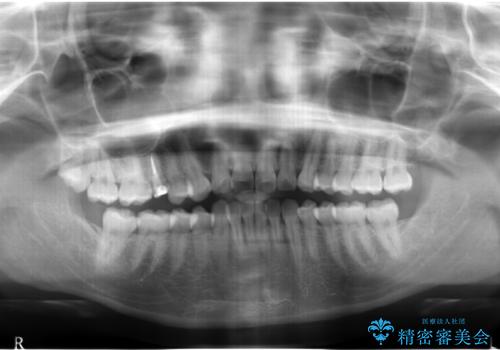

- 他院で治療途中、歯を被せたら頻繁に外れてしまうとのことでした。

診察すると、歯の高さがなく物理的に外れやすい状態となっていました。

歯周外科治療で歯の高さを出し、外れにくくしました。

奥歯の神経の治療および、土台は他院で行なっています。

セラミックにする前後でマウスピース矯正治療を行なっています。(以下のリンク参照)

- 21万円(右上4:ジルコニアクラウン10万円、仮歯 1万円、歯周外科治療(APF) 10万円、矯正用仮歯 2万円費用は治療当時の料金となります